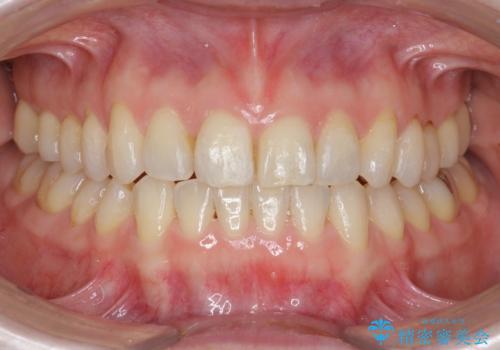

前歯の目立つガタつきをマウスピース矯正で治療

- 大きく傾いてしまった前歯のガタつきの改善を求めて来院されました。

前歯のガタつきをしっかりと取り、機能的・審美的に理想的な歯並びをマウスピース矯正で達成します。

強度のガタつきはマウスピース単体では並び切ることが難しいこともありますが、しっかりと装着していただいたことで良好な治療結果を得ることができました。